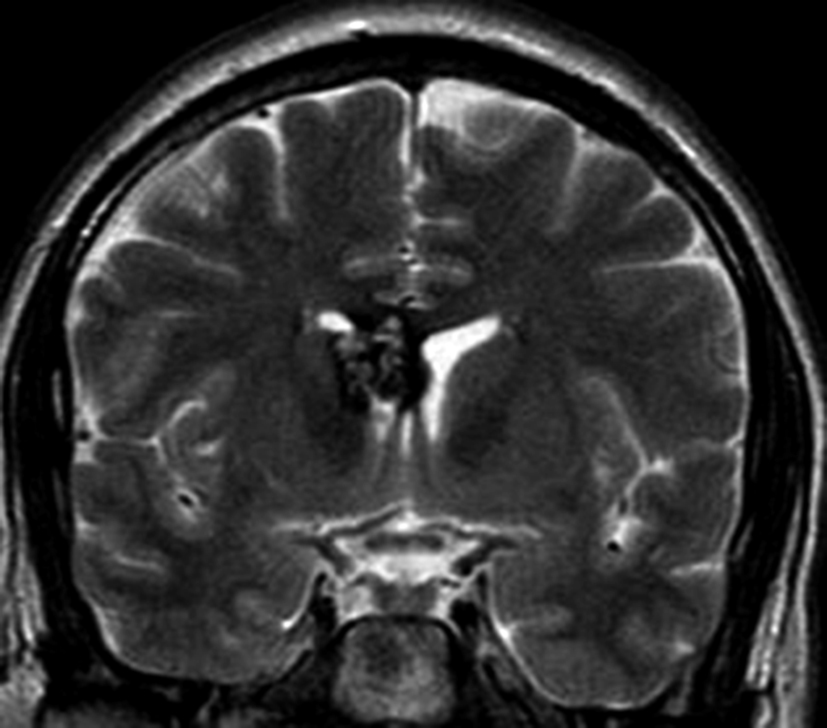

Se presenta el caso clínico de un paciente de sexo masculino, de 36 años de edad, sin antecedentes personales a destacar. Consulta por cefalea holocraneana de larga data, sin déficit neurológico y examen físico normal. Dada la clínica del paciente se realiza una tomografía computada de cráneo sin contraste intravenoso que identifica una lesión bien definida espontáneamente hiperdensa, heterogénea con calcificaciones puntiformes localizada en el asta frontal del ventrículo lateral derecho. No hay edema peri-lesional, efecto de masa ni hidrocefalia (Figura 1- A). Debido a los hallazgos se decide administrar contraste intravenoso, no evidenciándose realce significativo de la lesión (Figura 1- B).

Con los hallazgos tomográficos, no se efectúan planteos diagnósticos y se realiza una resonancia magnética con la finalidad de obtener más datos semiológicos en busca de una aproximación diagnóstica. Se realizó el estudio por medio de secuencias T 1, FSE T 2, FLAIR, SWI y Difusión, en cortes axiales, FSE coronal y sagital T 1. Se realiza la administración de gadolinio DTPA en los tres planos. Se evidencia la lesión bien definida a nivel del ventrículo lateral derecho, que involucra al tronco del cuerpo calloso (Figura 2- C y 3- B). Presenta intensidad de señal heterogénea en secuencias T1 y T2 (Figura 3 y Figura 4). En secuencia ecogradiente se observa una señal marcadamente hipointensa y heterogénea, con un halo hipointenso bien definido (Figura 2- C). No presenta realce significativo tras la administración de Gadolinio (Figura 2- B) y en la secuencia de difusión no presenta restricción.

Figura 3

a y b) Imágenes sagitales T1, A. se observa la lesión a nivel del asta frontal de ventrículo lateral derecho y B. se evidencia la extensión al cuerpo calloso.

Figura 4

a y b) Imágenes coronales T2, Ay B. se evidencia la lesión con epicentro en el asta frontal del ventrículo lateral derecho y la extensión al cuero calloso.